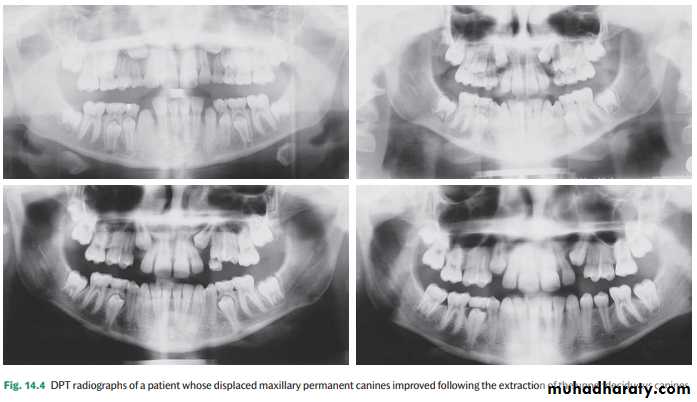

A number of studies have investigated the widely held belief that extraction of the deciduous canine facilitates an improvement in the position of a palatally displaced canine ( Fig. 14.4 ) where the unerupted tooth is not markedly ectopic.